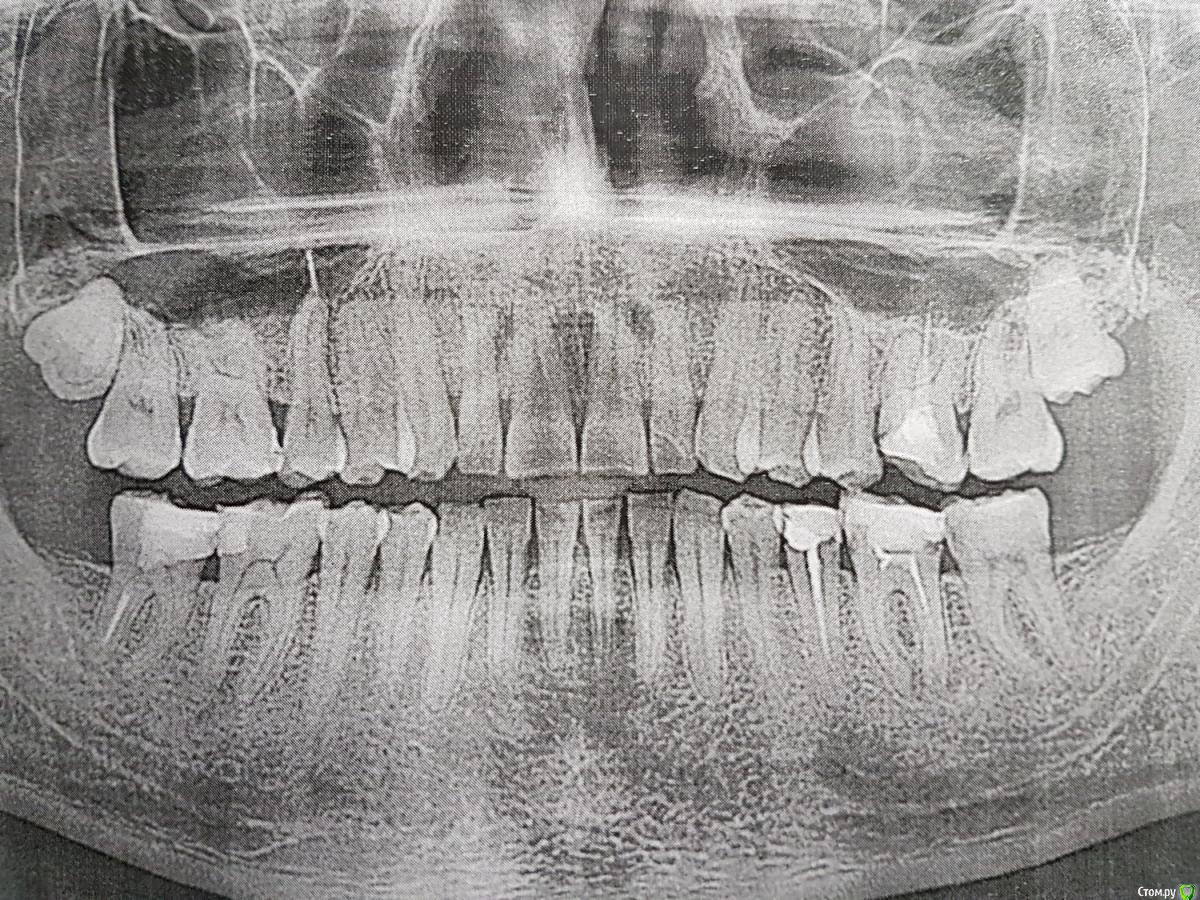

mozart Опубликовано 25 августа, 2016 Поделиться Опубликовано 25 августа, 2016 Добрый день. посмотрите снимок. Делал все 4 зуба один и тот же врач. два месяца назад делался крайний левый на снимке. потом через какое то время начал поднывать, если нажать на зуб. сейчас простыл и зуб резко заболел. ваши советы? Ссылка на комментарий

IvanK Опубликовано 26 августа, 2016 Поделиться Опубликовано 26 августа, 2016 Не лучший снимок.. Удаление 18,28Проф гигиенаПовторное лечение и протезирование 26,35,36,4716, 37,46 - нужно посмотреть с терапевтом Ссылка на комментарий